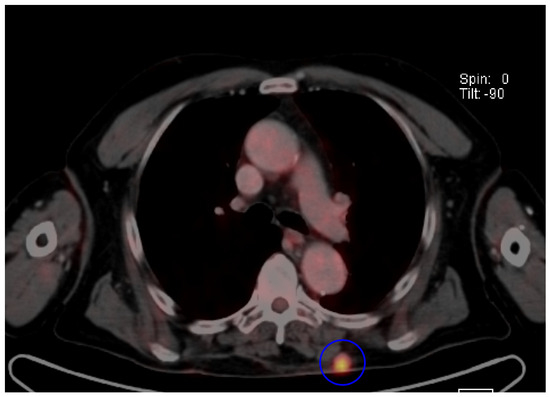

- Akaike, G.; Akaike, T.; Fadl, S.A.; Lachance, K.; Nghiem, P.; Behnia, F. Imaging of merkel cell carcinoma: What imaging experts should know. Radiographics 2019, 39, 2069–2084. [Google Scholar] [CrossRef]

- Oh, H.Y.; Kim, D.; Choi, Y.S.; Kim, E.K.; Kim, T.E. Merkel Cell Carcinoma of the Trunk: Two Case Reports and Imaging Review. J. Korean Soc. Radiol. 2023, 84, 1134–1139. [Google Scholar] [CrossRef]